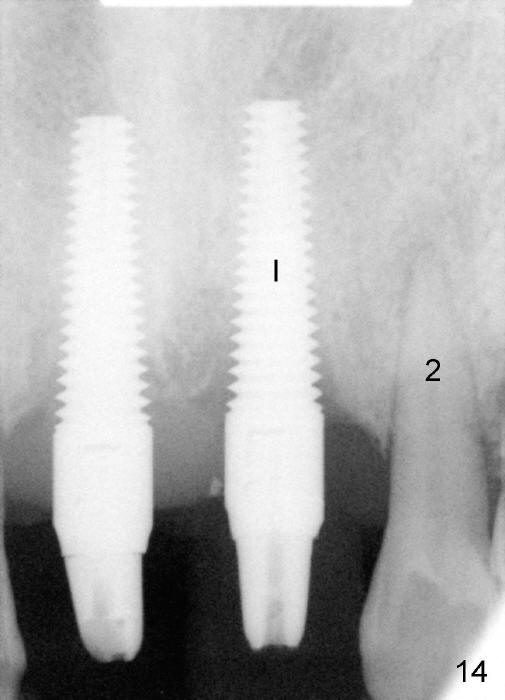

Four months post immediate loading, these two implants remain stable (Fig.14: I, longer and wider than the neighboring tooth (2)). The most surprising is that there is apparent bone regrowth distal to the implant at the site of the tooth #9.